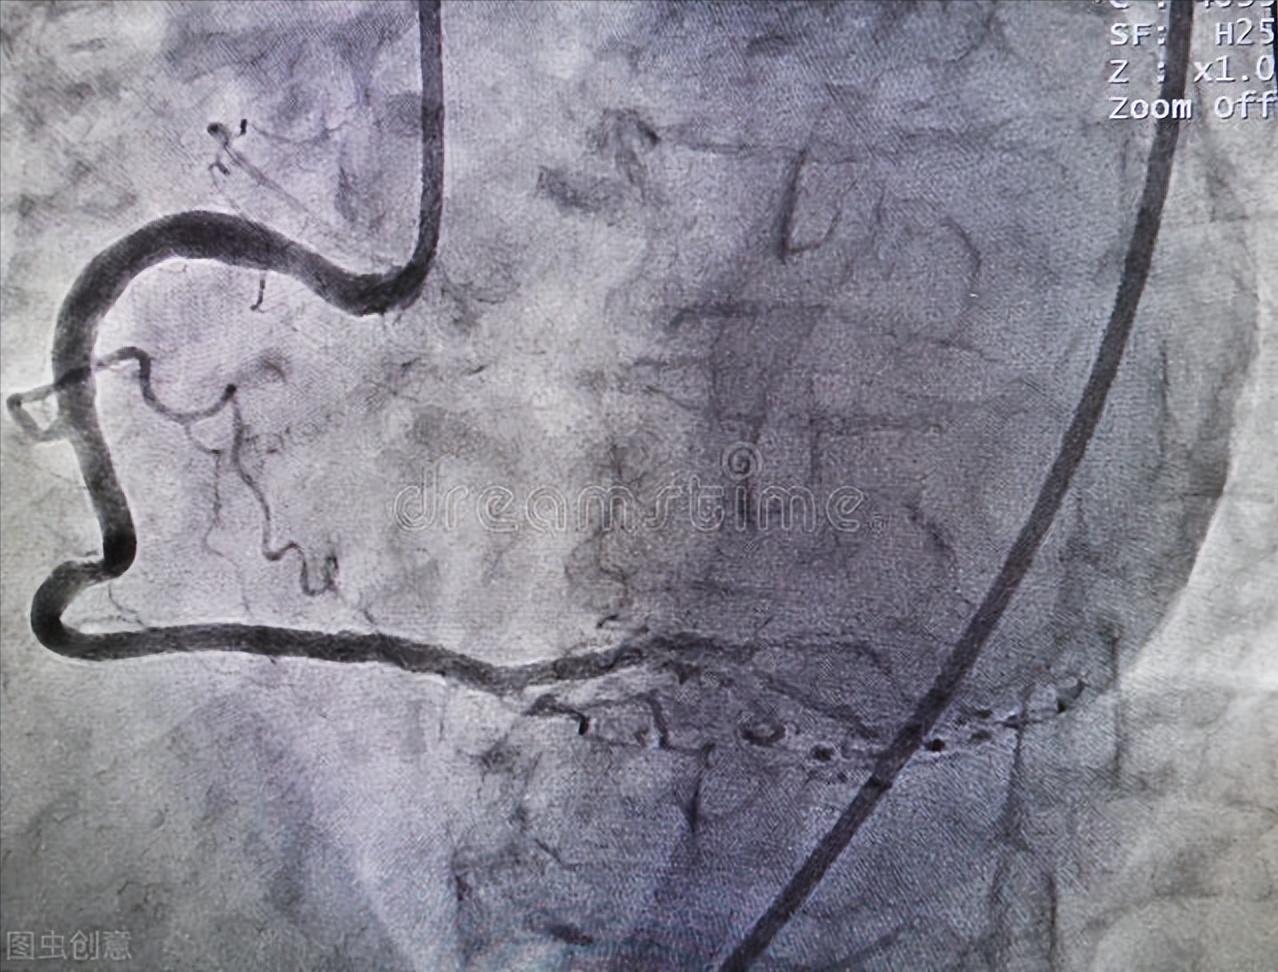

- 在造影导管到达冠状动脉开口后,通过注射器往冠状动脉推造影剂,另一边脚踩射线,这样就可以清晰地看到冠状动脉血管的走形,狭窄的地方也可以直观的看出来。

右冠状动脉